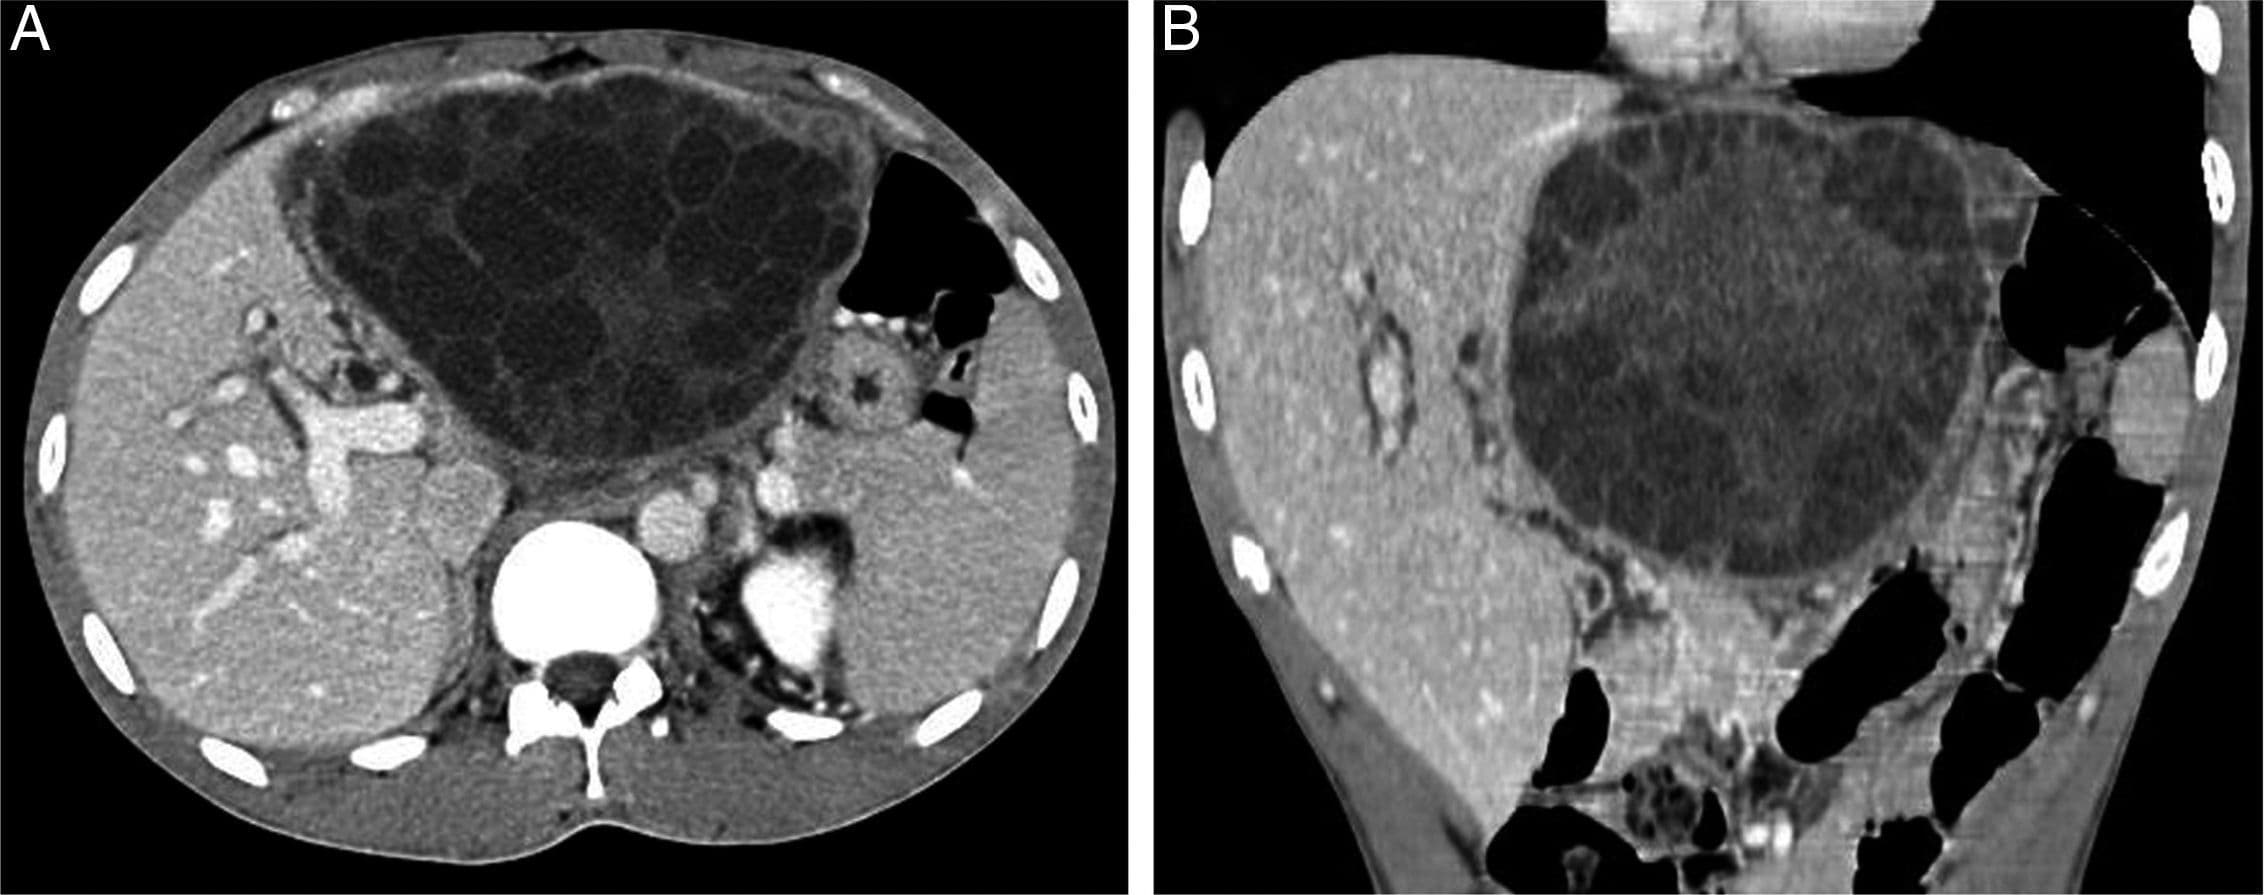

4. Quiste hidatídico:

El caso que hemos presentado se trata de un quiste hidatídico tipo II con la membrana desprendida. Os dejo imágenes con los diferentes tipos y el manejo de los mismos.